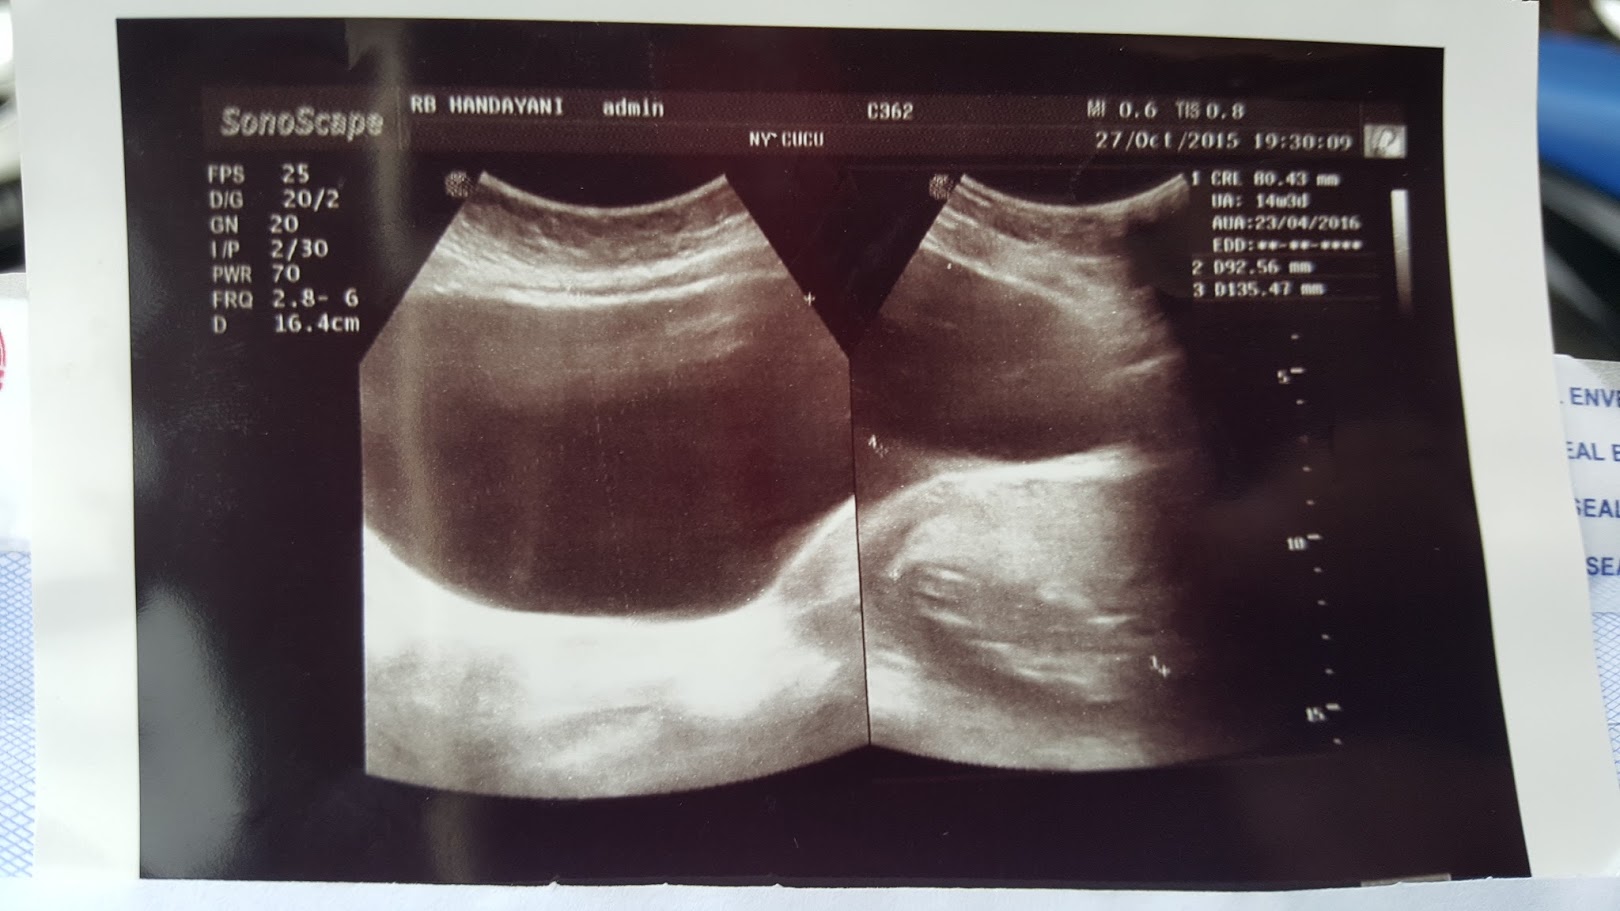

Assalamualaikum Bun , tadi saya baru usg soalnya bbrp

Assalamualaikum Bun , tadi saya baru usg soalnya bbrp

BILIK SONOGRAFER : Kista Ovarium

BILIK SONOGRAFER : Kista Ovarium